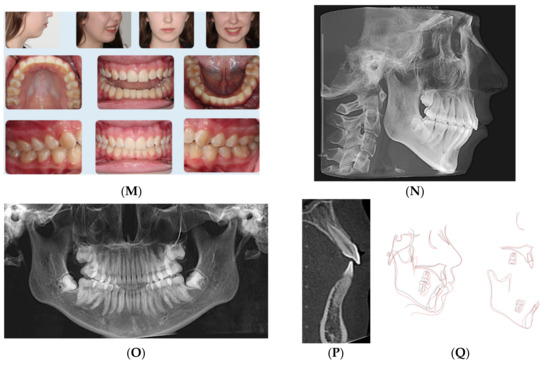

This 14-year-old female presented with chief concerns including severe dental crowding, increased overbite and overjet, and recessive chin. She and her parents were not interested in any surgical intervention for her recessive chin. Her medical history was not contributory, and her growth spurt was already passed as confirmed from her maturity indicator from CVM and physical/menstrual history. Her parents reported that she is a mouth breather and opens her mouth during sleep. Clinical records (Figure 3A–E) and cephalometric analysis (Table 3) revealed a convex profile with recessive chin.

Figure 3.

(A) Initial photographs showing convex profile with recessive chin and anterior crowding. (B) Initial digital models showing Class II Division 2 malocclusion with increased 5 mm overjet and impinging overbite. (C) CBCT-driven cephalometric radiograph showing convex profile with recessive chin and protrusive upper incisors. (D) CBCT panoramic radiograph showing the presence of permanent teeth; no other noticeable intraoral bony lesion could be detected. (E) CBCT-driven sagittal screen of lower incisor showing increased overjet and impinging overbite. (F) First digital treatment plan (ClinCheck) showing posterior teeth expansion and distalization. (G) Upper arch digital treatment plan (ClinCheck) showing expansion and distalization of posterior teeth (blue—initial teeth position, white—progress teeth position) and retraction of upper incisors to improve their initial protrusion. (H) Lower arch digital treatment plan (ClinCheck) showing (blue—initial teeth position, white—progress teeth position) lower arch expansion to allow lower incisor intrusion and leveling/alignment of lower incisor crowding. (I,J) Second digital treatment plan (ClinCheck) showing posterior teeth intrusion. (K) Upper arch digital treatment plan (ClinCheck) showing expansion of posterior teeth (blue—initial teeth position, white—progress teeth position) and retraction of upper incisors to improve their initial protrusion. (K) Lower arch digital treatment plan (ClinCheck) (blue—initial teeth position, white—progress teeth position) showing interproximal reduction between her lower teeth and lower incisor lingual movement to minimize anterior interference during forward rotation of the mandible as planned by the posterior teeth intrusion. (M) Final photos showing improved patient’s profile and chin projection as well as aligned upper and lower incisors and Class I buccal occlusion on both sides, improved overbite and overjet. (N) CBCT-driven final cephalometric radiograph showing improved profile and chin projection, although not ideal to straight profile, but patient and parents were satisfied with the results compared to initial clinical conditions. (O) Final CBCT-driven panoramic radiograph shows growing third molars to be followed for their eruption and possible removal if needed. (P) Final CBCT-driven sagittal screen radiograph of upper and lower incisors showing improved overjet and bone labial to both upper and lower incisors. (Q) Superimposition of cephalometric tracing of before (black) and after (red) treatment showing improved forward chin projection. However, challenges included vertical displacement of the mandible due to over-eruption of lower molars due to the patient’s mouth breathing habit and non-compliance of using the vertical-pull chin cup/Jaw Bra. Additionally, it shows lingual tipping of lower incisors.

The patient has a dolichofacial type with compensated Class II skeletal base relationship (ANB = 8.4°, SNB = 74.1°; FMA = 36.4°). Intraoral photos and digital models revealed a Class II division 2 malocclusion with increased overjet (5.5 mm) and impinging overbite (95%), as well as moderate upper and lower dental crowding (5 mm in each arch).

Treatment plan and progress: The patient and parents were made aware of the challenges of mouth breathing habit and its detrimental effects on treatment outcomes and stability. In addition, myofunctional therapy was proposed using a trainer for braces (T4B, Myobrace, Rancho Cucamonga, CA, USA) that was prescribed to be worn one hour during the day and night time with vertical-pull chin cup (Jaw Bra, Chanhassen, MN, USA). The treatment plan included sequential distalization of the upper posterior teeth utilizing light (3/16 3.5 ounce) Class II elastics for inter-maxillary anchorage and torqueing of upper incisors’ roots palatally. The vertical-pull chin cup together with occlusal coverage of the posterior teeth with the Invisalign aligners (working as posterior bite blocks) were intended to intrude posterior teeth. The first batch of aligners included 69 aligners; however, at stage 35 (Figure 3F–H), the patient was supposed to have molars in an end-to-end relationship, but due to the patient’s non-compliance, a decision was made to rescan the patient’s teeth for additional aligners that revealed the Class I molars over correction (Figure 3I–L). At that time, the patient was provided with VPro5 to use for 5 min per day to help with aligner seating if the patient experienced pain or if the aligners became ill-fitting due to long periods of time she was not wearing aligners during the day (12–16 h per day aligner wear per her report). The patient also could not use the Jaw Bra as prescribed, so the new additional aligners incorporated sequential posterior teeth intrusion to allow forward rotation of the mandible. In addition, the upper inter-premolars distances were expanded to correct the crossbite observed at stage 35 of the first batch of aligners (35/69). Lower incisor retroclination was prescribed using IPR of the lower incisors to help with minimizing anterior interference when the mandible was to be auto-rotated forward. When the patient used VPro5, she was able to change her aligners every 5–7 days considering her noncompliance with daily aligner wear (12–16 h of daily aligner wear).

When she used VPro5, her total treatment time was one year. Final records (Figure 3M–Q) showed maintenance of her vertical dimension (no change of FMA (Table 3)), improved apical-base relationship (ANB = 6.7°), lower incisor retroclination (IMPA = 87.5°). Although her mandibular apical base was moved forward (SNB = 76.7°), this improvement was counteracted by the lower posterior teeth extrusion (Figure 3Q) due to noncompliance with the Jaw Bra and existence of the mouth-breathing habit especially at night time. Overall superimposition shows the downward displacement of the mandible, which was due to extrusion of lower molars that could have been prevented by using the Jaw Bra.